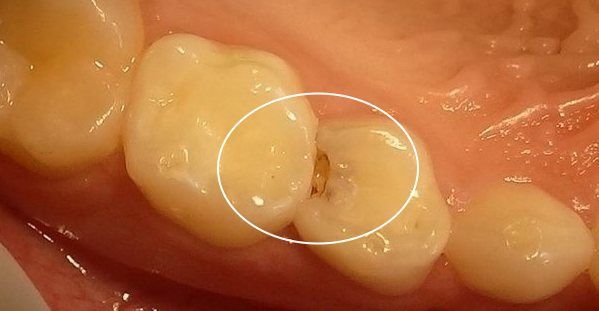

两颗牙齿接触的地方,看似密不可分,但它们之间其实是存在着间隙的。这些间隙很窄,你可能用肉眼看不出来。

同样地,因为间隙太窄,以至于你用牙刷都无法有效地清洁干净。

如果这些区域长期没有得到有效的清洁,细菌就会在里面扎堆生长,这最后的结果,很可能就会演变成蛀牙。